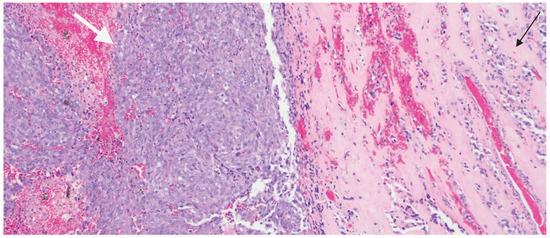

Unusual Dual Brain Tumor Morphologies in an MEN1 Patient: A Case Report of Diagnostic Challenges and Methylation Insights

Multiple Endocrine Neoplasia Type 1 (MEN1) is an autosomal dominant disorder commonly associated with tumor development in the parathyroid glands, pancreas, and pituitary gland. While pituitary adenomas are frequently observed in MEN1 patients, the presence of additional tumors within the pituitary gland is unusual. Moreover, the co-occurrence of a pituitary adenoma with an atypical teratoid/rhabdoid tumor (ATRT) has not been previously documented. ATRT is a rare, aggressive neoplasm predominantly affecting young children and is typically associated with inactivating mutations in the SMARCB1 or SMARCA4 tumor suppressor genes. These mutations result in uncontrolled cellular proliferation, which underlies the malignancy’s rapid progression. In adults, ATRT is exceedingly rare, making this case particularly noteworthy for its uniqueness in both tumor type and patient demographics. ATRTs are now classified into three molecular subgroups—MYC, SHH, and TYR—each with distinct epigenetic and clinical features, further refining diagnostic and prognostic assessments. In this case report, we describe a case of a female patient with MEN1 who experienced several recurrences of pituitary adenoma, ultimately necessitating surgical resection. Detailed pathological evaluation of the resected tissue revealed two distinct neoplasms within the pituitary gland: one typical of a pituitary adenoma, and the other confirmed as ATRT. The diagnosis of ATRT was established through extensive workup including immunohistochemical analysis, next-generation sequencing and methylation profiling, which served as essential tools in distinguishing ATRT from other potential differential diagnoses. This case illustrates the complex diagnostic journey and challenges encountered in identifying ATRT in the context of MEN1, underscoring the importance of using advanced molecular and immunohistochemical techniques in atypical presentations. Furthermore, it expands the understanding of potential tumor associations within MEN1, providing insight for pathologists and clinicians into the rare possibility of concurrent tumors in addition to pituitary adenoma in MEN1 patients. Raising awareness of such co-occurrences could prompt earlier diagnostic considerations by refining the differential diagnosis in patients with MEN1 presenting with unusual tumor types. Full article

Figure 1